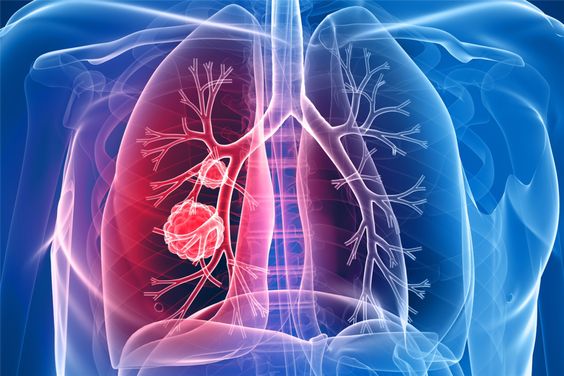

폐렴 증상 9. 입술이나 손끝이 푸르스름하게 변색 (청색증)

산소 포화도가 낮아지면서

입술, 손톱, 발끝이 보랏빛 또는 푸르스름하게 변하는 청색증이 생길 수 있습니다.

이는 폐렴이 상당히 진행된 상태일 수 있으므로 응급 상황입니다.10. 구토, 설사 등 소화기 증상